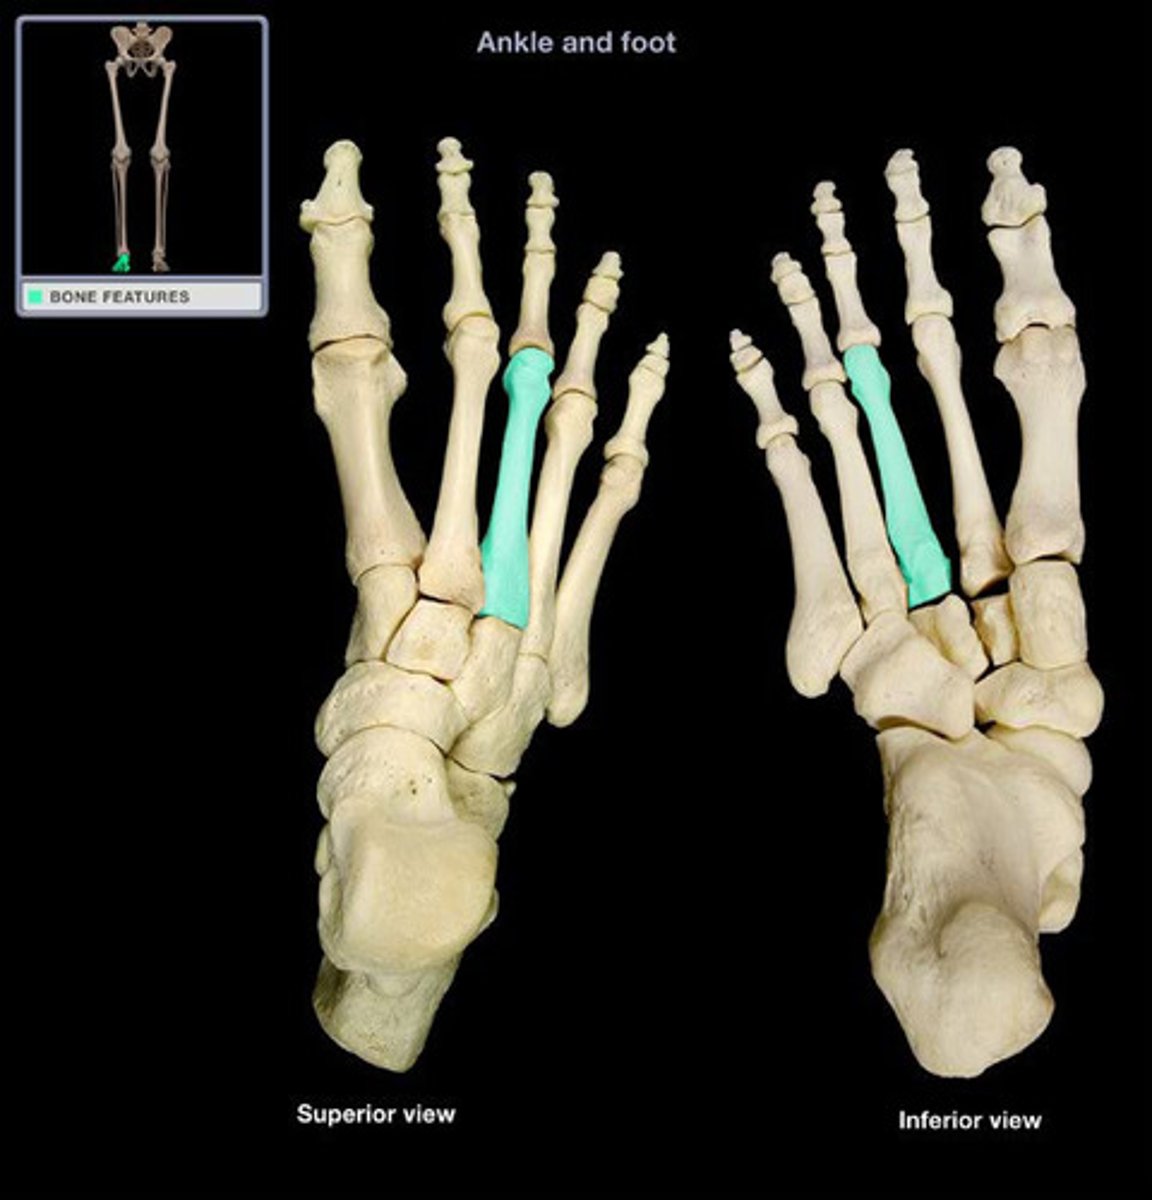

Third metatarsal